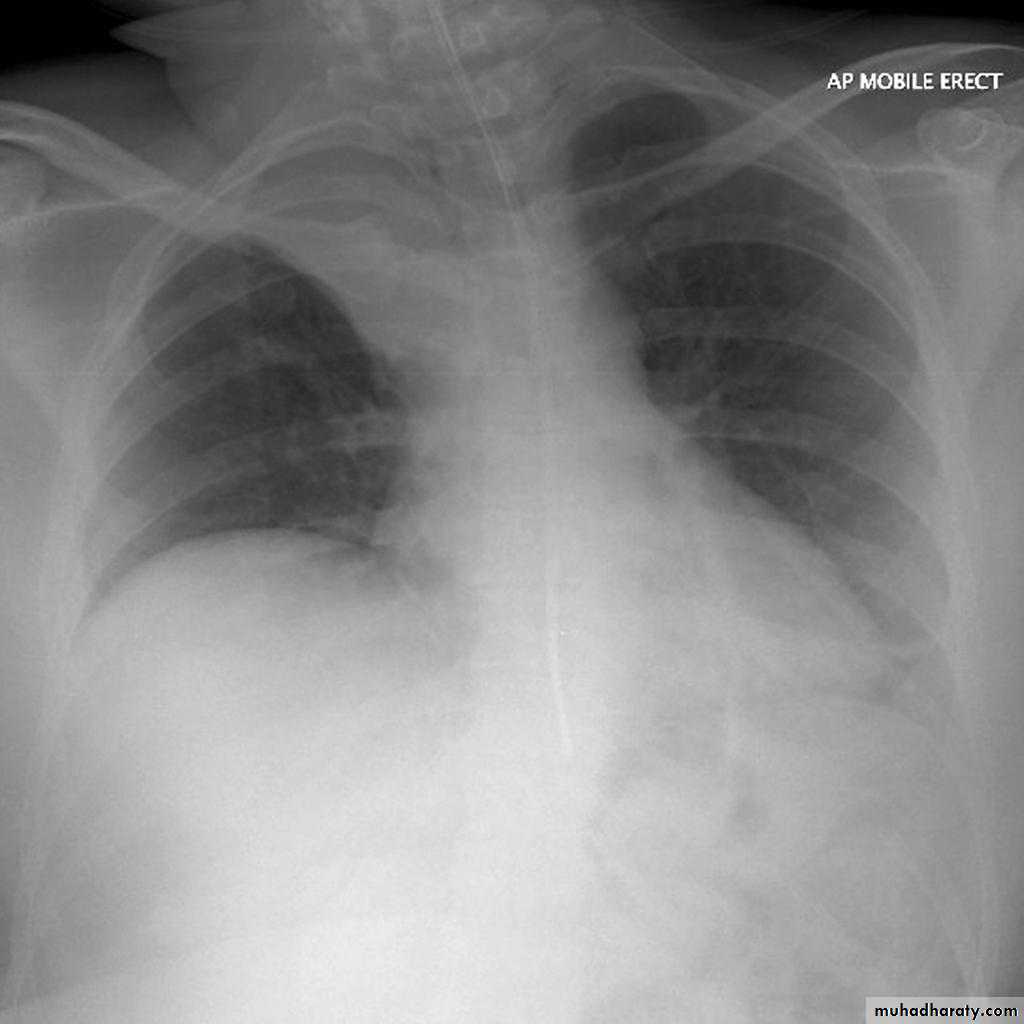

Left lower lobe collapse

is readily identified in a well penetrated film of a patient with normal sized heart, but can be challenging in the typical patient with collapse, namely unwell patients, with portable (AP) often under-penetrated films, often with concomitant cardiomegaly. Features to be observed include :

triangular opacity in the posteromedial aspect of the left lung

edge of collapsed lung may create a 'double cardiac contour'

left hilum will be depressed

loss of the normal left hemidaphgragmatic outline

loss of the outline of the descending aorta